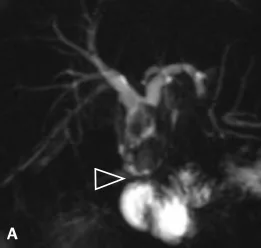

Figure 1. Patient exploré par bili-IRM pour une suspicion de migration lithiasique.

A. Cette coupe de bili-IRM 2D montre de multiples lithiases vésiculaires, ainsi qu’un calcul du bas cholédoque (tête de flèche).

B. Sur cette projection cholangiographique « MIP » issue d’une acquisition 3D en coupes fines, le calcul cholédocien est trop

petit au sein de cette VBP dilatée, et il n’est pas correctement visualisé. En cas de bili-IRM 3D, l’analyse de chacune des coupes

fines du volume est impérative. Ainsi, contrairement à la projection « MIP », la coupe fine passant par le cholédoque permet

de bien montrer le calcul (C)